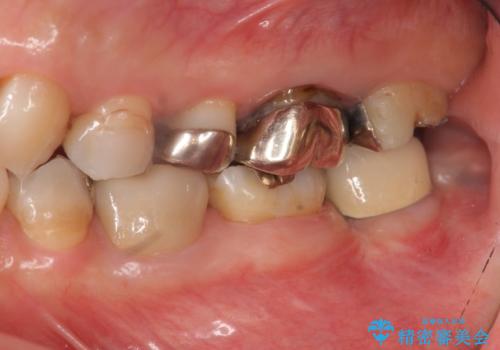

- 左下奥歯の咬合時疼痛を訴えて来院されました。

最後方臼歯周囲には大きな透過像が見られ、破折が強く疑われること抜歯が想定されることを理解していただき銀歯を除去したところ破折が認められたため抜歯を行いました。